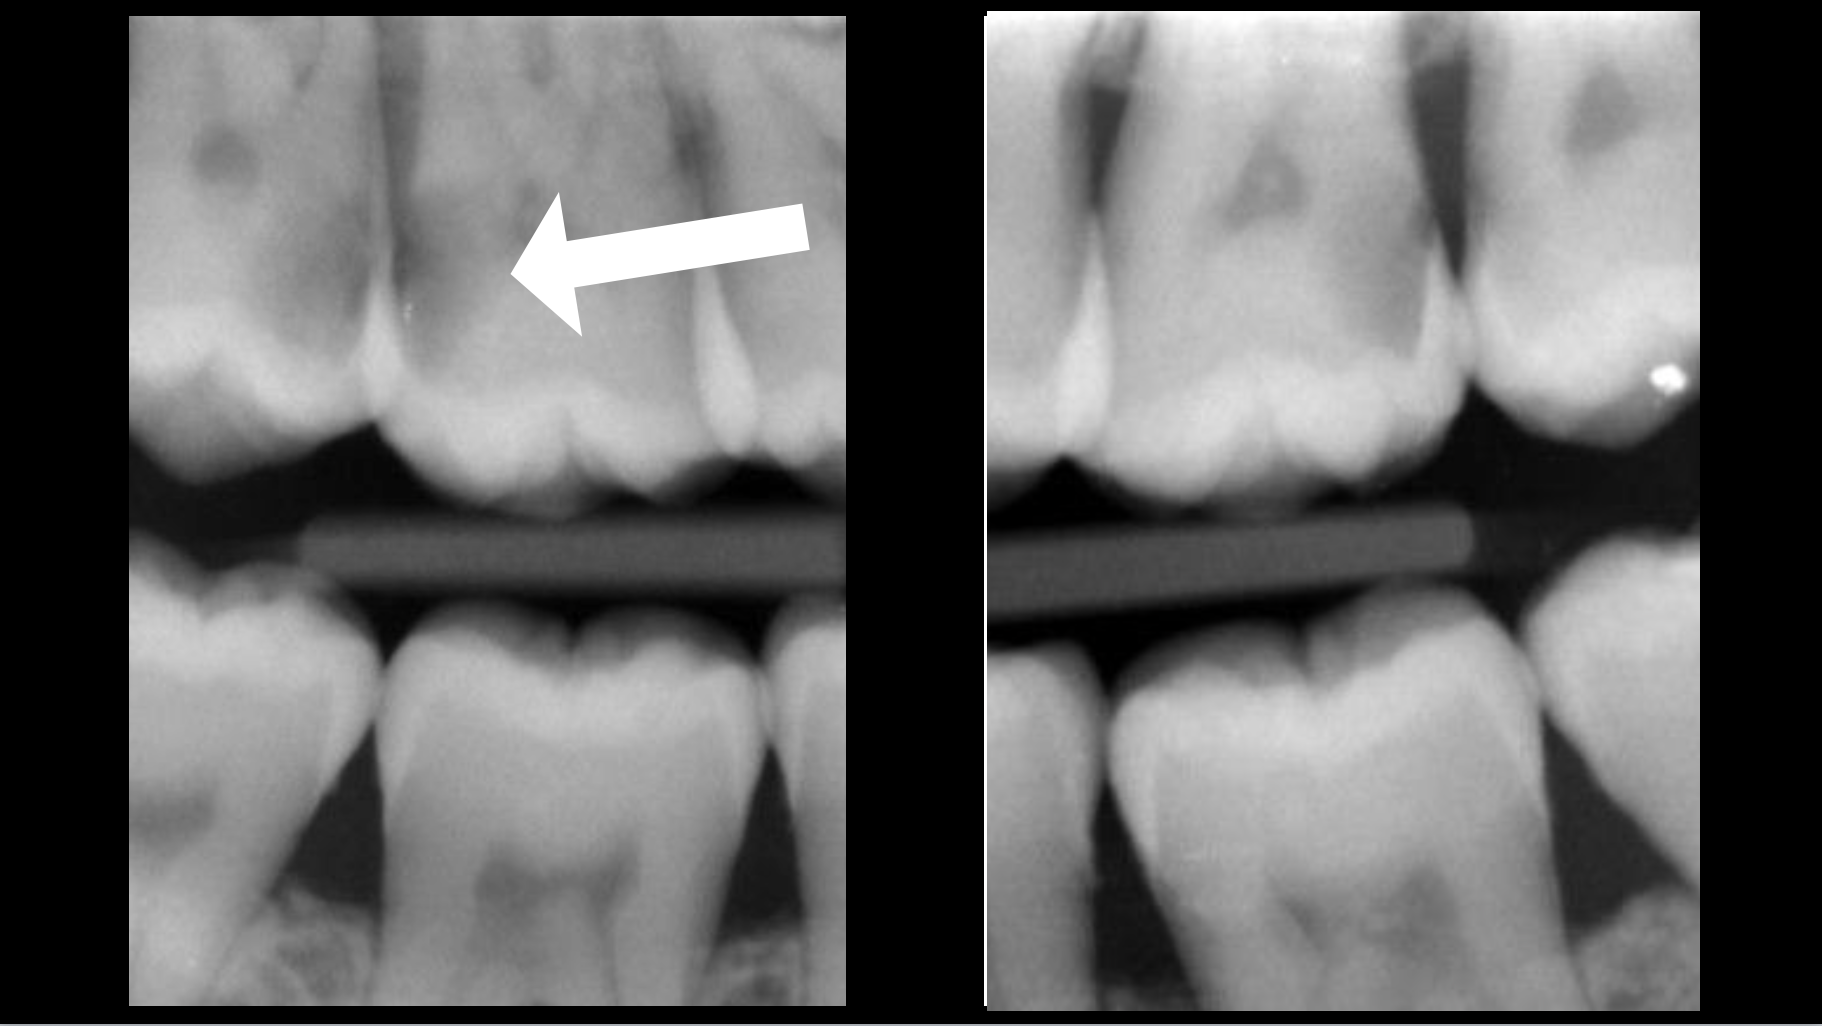

If the endodontium is infected, this pulpal necrosis may have caused an inflammatory reaction in the bone, known as an apical lesion:

In the absence of an apical lesion, the purpose of root canal treatment is to preserve healthy periapical bone.

When an apical lesion is present, the purpose of root canal treatment is to promote periapical bone healing.

Clinical case

Root canal treatment: 80–95% success rate